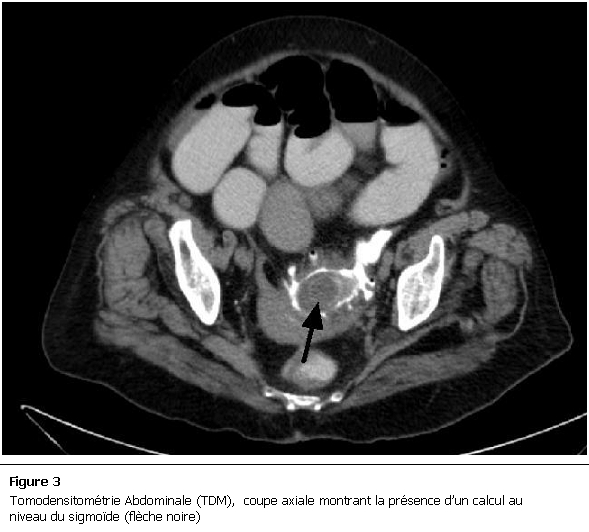

La malade a été mise en condition et une réhydratation a été débutée avec mise en place d’une sonde naso-gastrique avec compensation de la stase gastrique et surveillance de l’état HD et de la diurèse. Devant ce tableau de subocclusion inexpliquée, un scanner abdomino-pelvien a été réalisé et a objectivé des anses grêliques distendues, une aérobilie (Figure 2), et la présence d’un corps étranger de 5cm localisé dans le sigmoïde (Figure 3), le diagnostic d’iléus biliaire a donc été retenu. Devant l’absence des signes de gravité, l’amélioration de la fonction rénale quelques heures après le début des mesures de réanimation et devant la localisation distale du calcul, on a décidé de surveiller la patiente et de poursuivre le traitement médical.

Figure 3:

Tomodensitométrie Abdominale (TDM), coupe axiale montrant la présence d’un calcul au niveau du sigmoïde (flèche noire)